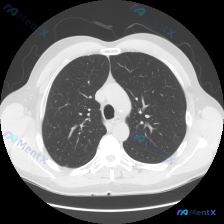

看到一个影像分析的矛盾病例,整理了一下思路: 首先是影像检查信息:这是胸部CT肺窗的横断面,报告提到双肺透亮度均匀,未见弥漫性磨玻璃影、实变或肺气肿;肺纹理清晰,支气管血管束走行正常;双侧胸膜光滑,纵隔居中,肺野清洁,未观察到结节、肿块等局灶性病变。 但输入里明确说了“Nodule(结节)”,这里就...

大家看一下这个病例,有点意思。用户的问题是“X光片上观察到了什么异常?”,还提到了关键词“结节”,但提供的却是胸部CT肺窗横断面的影像分析结果。 先整理一下CT分析的核心信息: - 扫描层面:主动脉弓下方至气管分叉上方水平 - 双肺:视野清晰,肺实质内未见明显的片状实变影、磨玻璃影或结节影,肺血管纹...